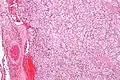

Micrograph of a carotid body tumor (a type of paraganglioma).

The paragangliomas appear grossly as sharply circumscribed polypoid masses and they have a firm to rubbery consistency. They are highly vascular tumors and may have a deep red color.

On microscopic inspection, the tumor cells are readily recognized. Individual tumor cells are polygonal to oval and are arranged in distinctive cell balls, called Zellballen.[8] These cell balls are separated by fibrovascular stroma and surrounded by sustentacular cells.